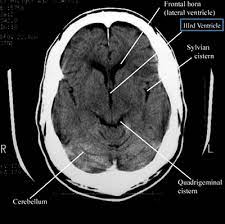

Enter the transformative role of the head CT scan, a diagnostic tool that offers clarity and peace of mind. A head CT scan, or computed tomography, is a non-invasive procedure that captures detailed images of the brain. This technology is crucial in diagnosing conditions such as tumors, brain injuries, and other abnormalities. For Radhika and many others, it provides a definitive answer, replacing the fear of the unknown with a clear path forward.